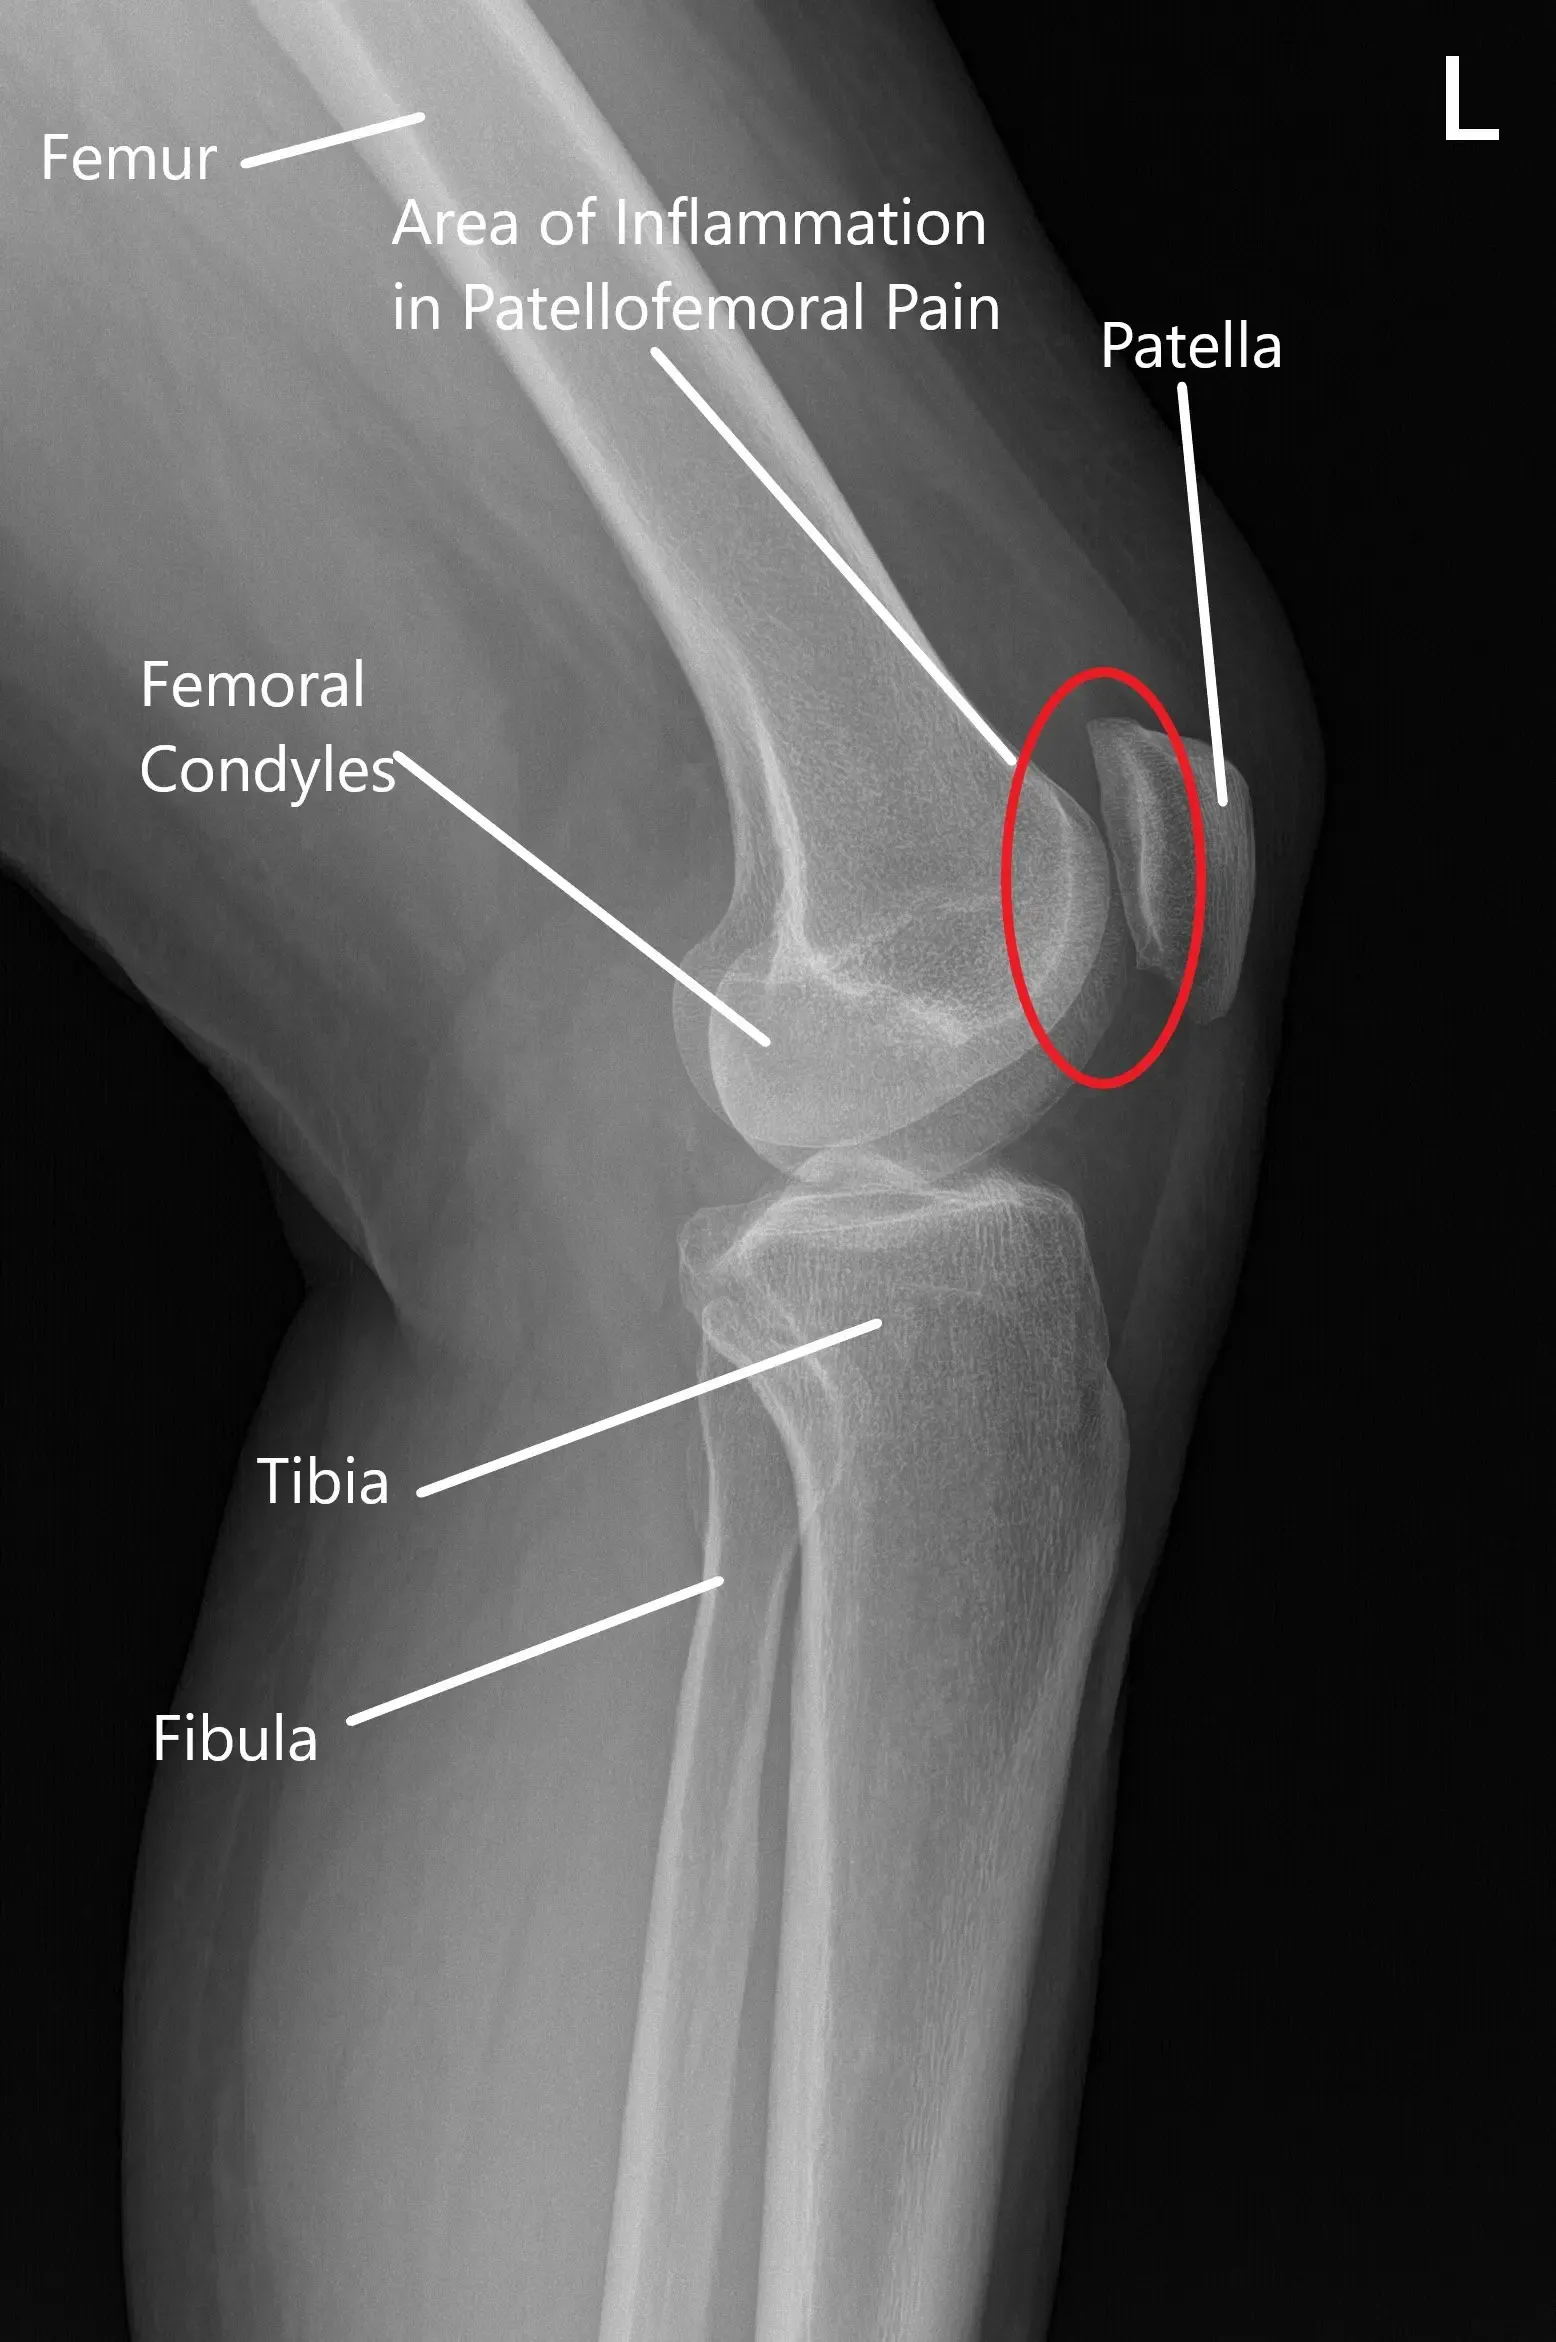

How the Body Part Normally Works? (Relevant Anatomy)

The patellofemoral joint is where the patella (kneecap) rests within the groove of the femur (thigh bone). The knee joint functions by allowing smooth bending and straightening movements, with the patella helping to stabilize and guide these motions. In PFPS, the alignment of the kneecap becomes compromised, often due to muscle imbalances, tight ligaments, or poor training, leading to pain and discomfort.

Normal X-ray of the knee joint showing the various structures in the Anteroposterior and Lateral view.

X-ray showing Skyline’s view of the patella.